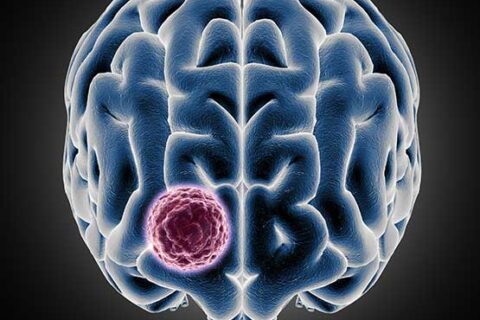

ΟΓΚΟΣ ΕΓΚΕΦΑΛΟΥ & ΣΠΟΝΔΥΛΙΚΗΣ ΣΤΗΛΗΣ

Εκτομή όγκων εγκεφάλου και Σπονδυλικής Στήλης με τη χρήση νευροπλοήγησης και διεγχειρητικού υπερήχου